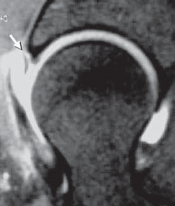

Labral repair is best suited for young patients when it is believed that simple débridement may result in inordinate sacrifice of healthy tissue ( TECH FIG 2).

An optimal pattern is a tear at the articulolabral junction where a large segment of otherwise healthy tissue has been detached.

Labral function is most dependent on its fluid seal.2 Thus, the goal of repair is to reapproximate the labrum to the adjacent acetabulum.

The mechanical properties of the labrum are minimal; therefore, the recreation of a bolster effect such as that in the shoulder is not necessary.

A D E TECH FIG 2 • A. Sagittal MRA image demonstrates an anterior labral tear (

). B. Arthroscopy reveals a traumatic detachment of the anterior labrum (indicated by the probe). C. An anchor has been placed with suture limbs passed in a mattress fashion through the detached labrum. D. The labrum has been reapproximated to the articular edge. E. Viewing the peripheral aspect of the labrum, the suture is seen on its capsular surface, avoiding contact with the articular surface of the femoral head. (Courtesy of J. W. Thomas Byrd, MD.) ### TECHNIQUES

1. An anchor should be placed adjacent to the articular edge; it is not necessary for it to be placed on its surface.

The angle created by the articular surface and the bony edge of the acetabulum is more acute than its counterpart in the shoulder, which is created by the articular surface and bony face of the glenoid.

Thus, the direction of anchor entry is more critical, especially to avoid perforation of the articular cartilage. This direction is dictated by the position of the cannula.

The standard portal placements lend themselves well to anchor placement, but if the direction of entry does not seem appropriate, it is best to simply establish another portal with the proper angle for anchor entry.

The anchor is seated adjacent to the articular surface, between it and the detached labrum.

Passage of the suture limbs through the detached labrum can then be accomplished with various suture-passing devices.

It is important that the sutures not be left interposed between the labrum and the articular surface of the femoral head, because this can result in third-body wear on the articular cartilage.

Passing the sutures in a mattress fashion accomplishes reapproximation of the labrum, recreating the seal and avoiding interposed suture in the joint. #### CHONDROPLASTY